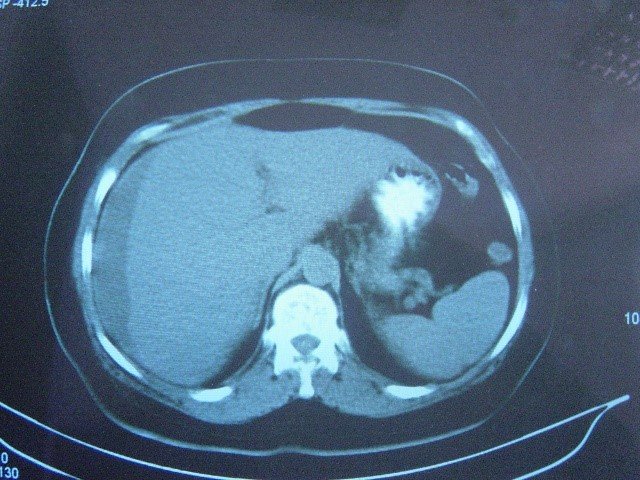

- KT peritonitin səbəbini müəyyənləşdimədə standart müayinədir. Qarında maye, sərbəst hava,± kontrast ekstravazasiyası, orqan patologiyaları peritonitin xarakterik əlamətləridir.

- USM/KT – də qarında maye, hava, kontrast ekstravazasiyası və orqan patologiyaları.

- KT – məhdud və ya diffuz maye, periton qalınlaşması, bağırsaq və digər orqanlarda infiltratlar, omentumda düyünlər

- KT- məhdud və ya diffuz maye, periton qalınlaşması, bağırsaq və digər orqanlarda infiltratlar, omentumda düyünlər